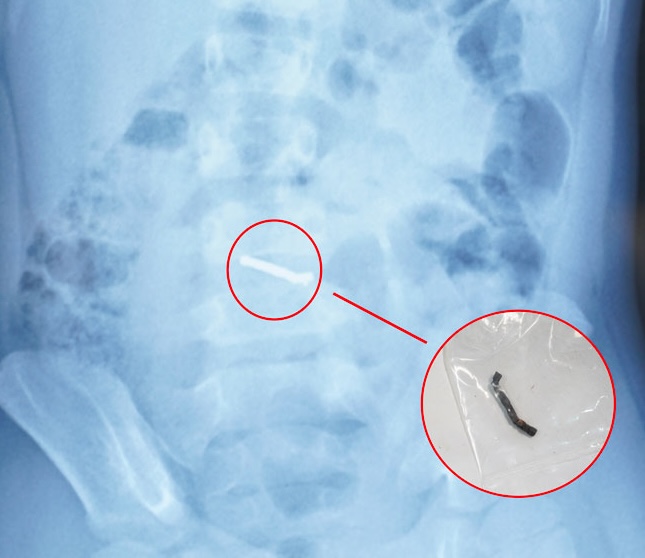

自宅で薬を服用している間、症状は改善せず、子供は再診を受け、腹部に異物が発見されたX線写真が撮影されました。その後、子供は経過観察と治療を続けるために中央小児病院に転送されました。

しかし、この場合、異物は動かなかった。家族から提供された、小さな磁石が互いに吸い合うことができるおもちゃの種類に関する情報から、医師は子供が何度も磁石を飲み込んだと診断した。異物が磁性であり、自然に排出できないと判断した後、医師は子供に手術を行った。

手術中、医師は多くの小さな磁石が鎖状にくっついており、腸に穴が開いていることを発見しました。外科医は異物を除去し、穴を縫合し、ドレーンを挿入しました。4日後、患者は正常に生活し始め、食事の練習を再開し、数日以内に退院する予定です。